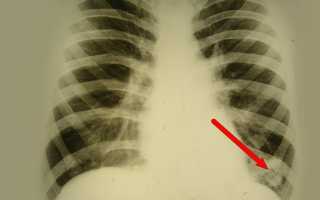

Хронический абсцесс легкого может возникнуть вследствие осложнения инфекции или туберкулеза. Врачи отмечают, что основными симптомами этого заболевания являются кашель с гнойным отхаркиванием, боль в груди, повышенная температура тела и общая слабость. Для диагностики абсцесса легкого необходимо провести рентгенологическое исследование, компьютерную томографию и бактериологические анализы мокроты.

Хронический абсцесс легкого – серьезное заболевание, вызванное образованием гнойного полости в легочной ткани. Основные причины его возникновения связаны с инфекцией, чаще всего вызванной бактериями. Симптомы включают кашель с гнойной мокротой, боль в груди, лихорадку. Диагностика проводится с помощью рентгена, компьютерной томографии и бактериологических исследований. Лечение включает антибиотики, дренирование абсцесса и в некоторых случаях хирургическое вмешательство. Важно обратиться к врачу при первых признаках заболевания, чтобы избежать осложнений.

Хронический абсцесс нужно дифференцировать от туберкулеза, актиномикоза, полостной формы периферического рака легкого. Основная диагностика проводится по тем же принципам, что и при подозрении на острую форму гнойного воспаления. У большинства пациентов с хроническим абсцессом в анамнезе обнаруживается перенесенное ранее гнойно-деструктивное воспаление. Диагностика включает следующие исследования:

- рентгенологическое исследование;

- компьютерная томография легких;

Для постановки диагноза пациенту предложат сдать анализ крови и мочи, проведут анализ выделяемой мокроты и бактериоскопию с бакпосевом, что позволит точно выявить возбудителя и определить его чувствительность к медицинским препаратам. Также проводится рентгенография легких, КТ и МРТ легких и ряд других исследований.